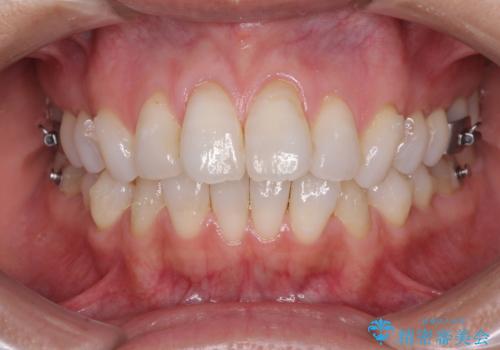

少しだけ飛び出た前歯を整えたい インビザラインによる矯正治療

- 少しだけ前に飛び出ている前歯を気にして来院された患者様です。

上顎歯列全体を後方に移動させる必要があり、インビザライン単体での治療は困難と判断し、補助装置により左右側方歯列を移動させた後にインビザラインを用いることとしました。